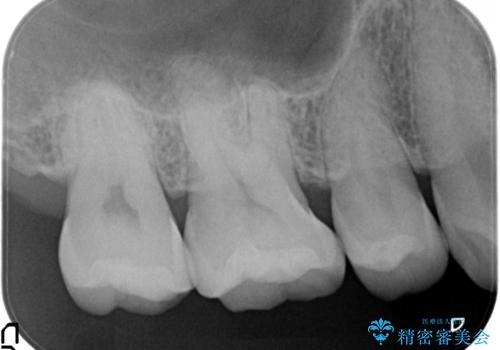

e-max プレスインレーにて修復治療を行っているため適合性及び審美性の高い治療を行うことができます

- 天然歯を削ります

- 硬い素材は天然歯を傷つけてしまう場合があります

- かみ合わせや歯ぎしりが強すぎる方はセラミックが割れてしまう可能性があります